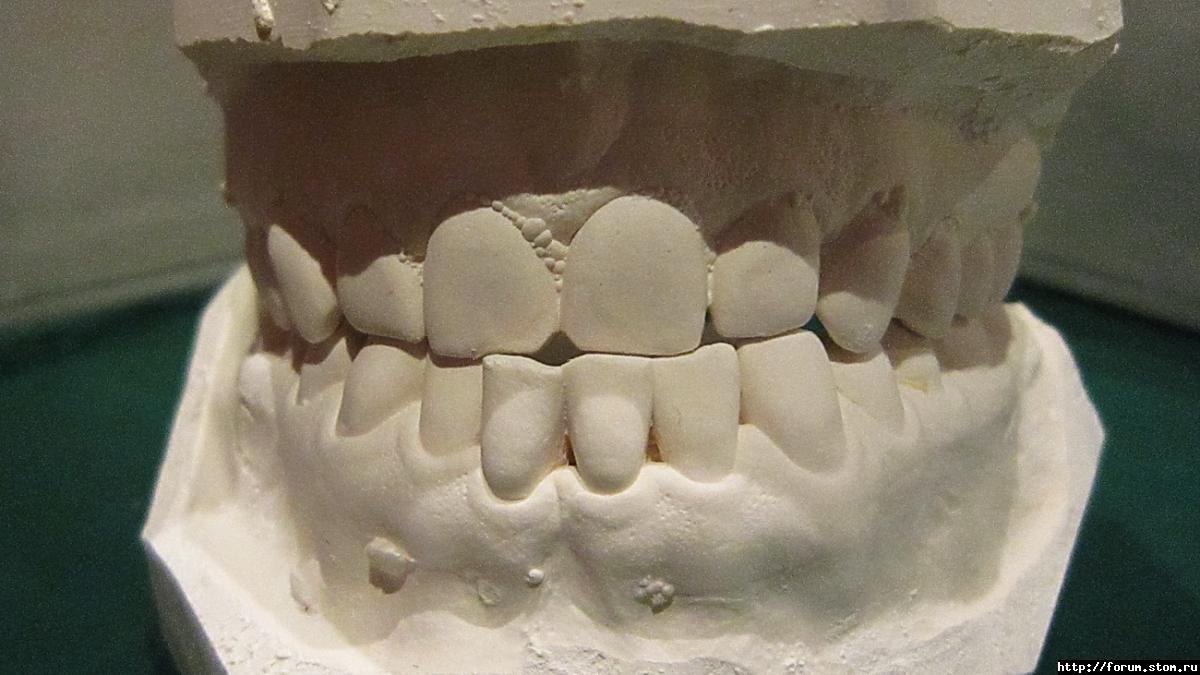

Inn-ka Опубликовано 6 ноября, 2011 Поделиться Опубликовано 6 ноября, 2011 (изменено) Добрый день, Уважаемые.Есть проблема - мезиальный прикус, передие нижние зубы перекрывают верхние.Мне 30, понятное дело, если ставить брекеты - хотелось бы лингвальные.Не совсем понятно - целосообразно ли, при моей проблеме ставить лингвалки.Пока была на консультации только у одно ортодонта.Доктор долго мялась, говорила: "эх, сделать быть операцию, чуть-чуть чик и все"."чикать" не получится, операцию мне делать нельзя.Да и масштаб проблемы не такой, чтобы решиться на такие кардинальные меры.Затем, доктор сказала: "ну ладно, тогда установим микроимплант и будем нянуть зубы в обратном направленинии".В общем - ищу других докторов, хочу услышать различные мнения.Понимаю, что мой волевой подбородок останется при мне, да и не отраляет от мне жизнь.Мне бы зубы выровнять. Это-то, надеюсь возможно?Кстати, энное количество времени назад одну нижнюю восьмерку удалила, смотрю, скученность со стороны удаления восьмерки, стала менее выражена. Собираюсь с духом удалить вторую. Уж очень травматично и болезненно в первый раз получилось. :-(Буду очень благодарна специалистам за советы. Изменено 6 ноября, 2011 пользователем Inn-ka Ссылка на комментарий

Премоляр Опубликовано 6 ноября, 2011 Поделиться Опубликовано 6 ноября, 2011 "Мне бы зубы выровнять. Это-то, надеюсь возможно?"-конечно возможно Профиль конечно не изменить,ибо работа будет только на зубоальв.уровне путем компенсации.С точки зрения эстетики вас устроит результат,но с точки зрения функции и стабильности результат может не устроить доктора Ссылка на комментарий

Force Опубликовано 6 ноября, 2011 Поделиться Опубликовано 6 ноября, 2011 Без операции возможно пролечить либо с удалением премоляров нижней челюсти, что не есть хорошо, либо с использованием техники многопетлевой дуги. До http://i051.radikal.ru/1109/68/9299be8a9a53.jpg После http://s009.radikal.ru/i307/1109/30/2152edffbc4f.jpg В последнем варианте профиль меняется незначительно, но эстетика и функция восстанавливаются. К сожалению, о лингвальных брекетах речи и быть не может.(только вариант 1, но там много нюансов). Ссылка на комментарий